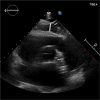

Methods: We retrospectively included consecutive patients undergoing diagnostic coronary angiography as well as transthoracic echocardiography between March and October 2016. EAT thickness was defined as space between the epicardial wall of the myocardium and the visceral layer of the pericardium and EAT index was calculated as EAT thickness/body surface area. Logistic regression analysis was used to determine the association of EAT index with the presence of CMD.

Figures